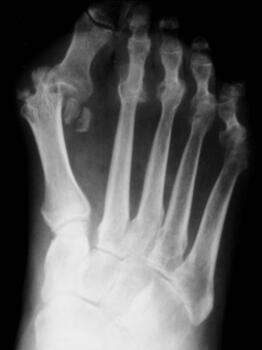

• A 2019 study in Current Rheumatology Reviews which observed that metformin may protect bones, especially during the early stages of rheumatoid arthritis, and decrease inflammation, risk of cardiovascular disease and cancer in patients with rheumatoid arthritis;16

• A 2019 study indicated that the use of metformin may have a beneficial effect on long-term knee joint outcomes in those with knee osteoarthritis and obesity. Researchers noted that randomized controlled trials are necessary to validate these findings and ascertain whether metformin would be a potential therapy.18